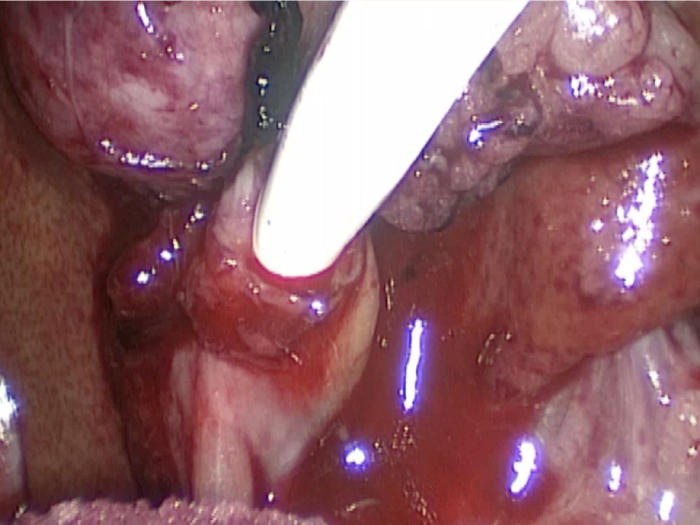

胆嚢が破裂した様子を腹腔内にカメラを入れて観察した像です。

胆嚢から漏れ出た胆汁が腹腔内に確認できます

胆嚢の周囲の脂肪や膵臓、十二指腸が激しく癒着し剥離が困難な状態でした。 胆嚢は全く確認することができませんでした。

癒着(矢印)がひどく胆嚢を確認することができませんでした。

このように癒着しているときはギリギリで剥がすとひどく出血をおこすことがあるので無理にはがそうとしないで、脂肪の血管に注意しながら脂肪ごと剥がしていきます。